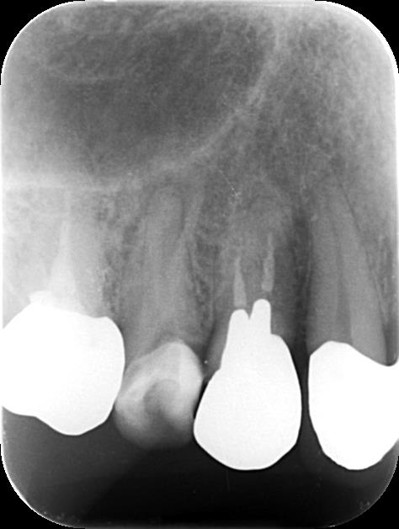

ファイル除去後 ![]() |

精密検査の結果、折れた器具の見える位置にありますのでマイクロスコープを使い、自費診療の器具を用いれば除去できる可能性があります。 |

精密な機材を用いても、器具の状態によっては安全に除去しきれない場合があります。 |